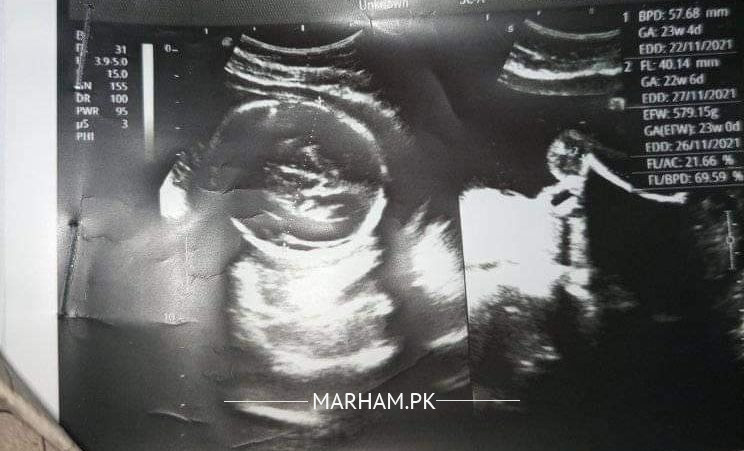

Asking For Sister, Female 25, karachi

Please check my report everything is fine

Can you tell me what's the gender we are very excited for baby girl so can you check it

Total ktne weeks ho gae hn pregnancy ko

23 weeks can you see the gender?

In this Pic can you see the gender?

Seems normal pregnancy of 23 weeks (6 months ) .